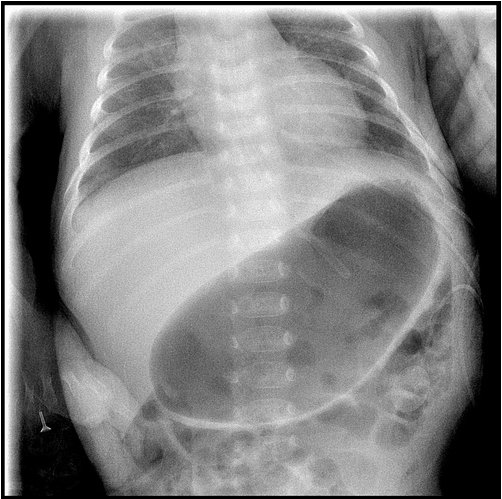

▲腹部X光顯示寶寶的胃部很脹,無法通過幽門到達十二指腸的食物皆堵在胃裡。

「嬰兒肥厚性幽門狹窄」顧名思義是幽門肌肉增生致通道變窄,食物無法通過幽門到達十二指腸,全部堵在胃部裡,當胃盛裝不下食物,便會從食道噴濺出來。因無法真正攝取營養,罹患嬰兒肥厚性幽門狹窄的嬰兒通常會體重較輕,甚至比剛出生時還要輕。楊筱惠醫師指出,引發嬰兒肥厚性幽門狹窄的原因未明,發生率約在2%-4%,且男嬰的發生率是女嬰的四至六倍,尤其以第一胎男嬰機率最高。

楊筱惠醫師指出,典型的嬰兒肥厚性幽門狹窄最容易辨認的特徵,就是剛出生時喝奶情況會較順利,但在三週至三個月大之間,反而開始出現明顯嘔吐情形,幾乎餐餐餵完就出現「噴射性」嘔吐,吐出的是無膽汁奶水(即未消化過的),且症狀越來越嚴重。新生兒沒有馬上出現症狀,主要是剛出生時的幽門是正常的,隨著時間越長越大,肌肉肥厚的情況加劇,才會逐漸出現症狀。